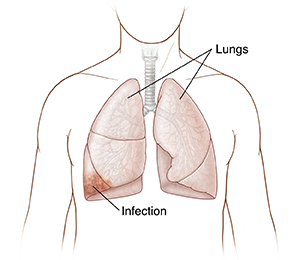

Infections

Infections are illnesses caused by bacteria, viruses, or fungi. Examples of lung infections include tuberculosis and pneumonia. Lung infections can cause fluid to build up in the lungs or chest. Some lung infections are spread from person to person through the air. Most lung infections can be treated with antibiotics if they are caused by bacteria. Or they may be treated with other medicines.